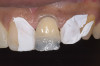

During the next appointment, a palatal index of the approved provisional was fabricated with putty silicone. This enabled the clinician to precisely build the lingual surfaces and incisal edges of teeth Nos. 6 through 11. The provisional mock-up resin on No. 9 was removed, and the underlying labial tooth was roughened with an abrasive diamond bur. No tooth structure was removed from the palatal surface, and unsupported enamel was rounded off from the labial. An ultrathin dry cord was placed in the gingival sulcus on No. 9 (Figure 9 and Figure 10). Teflon tape was used to isolate No. 9 from adjacent teeth. Then 37% phosphoric acid was used to totally etch the labial surface for 10 seconds and the palatal surfaces on No. 9 for 5 seconds. Single bond was applied and spread uniformly across the tooth and light-cured for 20 seconds.

White enamel shade was placed on the putty index and carried to the palatal surface of No. 9. This layer was spread uniformly and thinned out and spread along the entire width of the tooth (Figure 11). After curing this layer, A2 dentin was layered to simulate the lobular pattern seen in dentin of the natural teeth (Figure 12). After curing, a layer of transparent resin was placed in the incisal areas between the dentinal lobes. The final layer of A2 enamel was built and shaped to full contour (Figure 13). A similar build-up was done for all the remaining anterior teeth. The bite in MIP was adjusted such that there was uniform contact on all anterior teeth. The anterior guidance was harmonized to maintain uniformity in the contact of the incisors during protrusion and the canines and incisors during lateral excursions. Finishing and polishing was done per protocol (Figure 14 through Figure 18).13